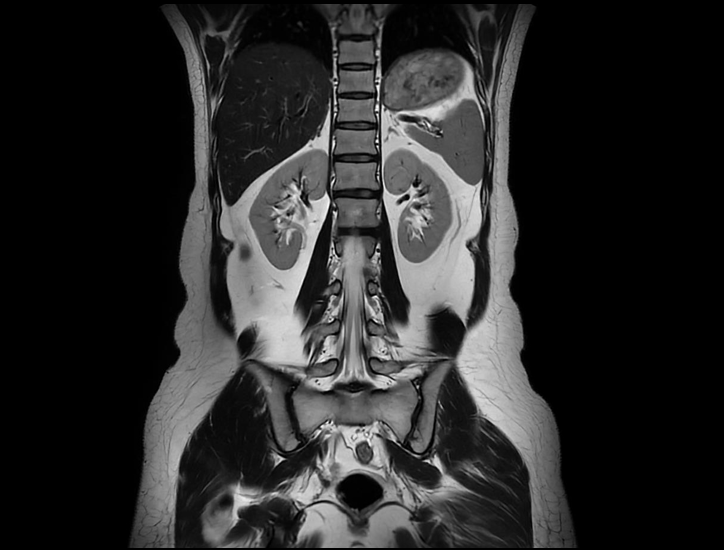

Boundless Clinical Scenarios

uMR Omega™은 uAIFI 기술 플랫폼의 지원을 받아, 상당한 성능 향상, 강력한 이미징 능력, 개선된 작업 흐름 및 향상된 사용자 경험을 통해 많은 기대를 받고 있습니다.

Technology Required for Ultra-wide Imaging

3.5MW의 최대 출력을 갖춘 차세대 GPA.

45mT/m 및 200 T/m/s의 그라디언트 성능.

0.029ppm @30 DSV 균일성 (일반적인 값).